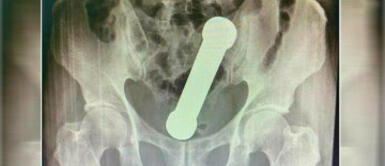

La imagen arrojó que se trataba de un caso inusual de "naturaleza sexual". El hombre hizo llegar un objeto hasta su ano durante un momento de masturbación. Este objeto era nada menos y nada mas que una mancuerna, de unos 20 cm, alojada entre el colon y el recto.

Foto: International Journal of Surgery Case Reports.